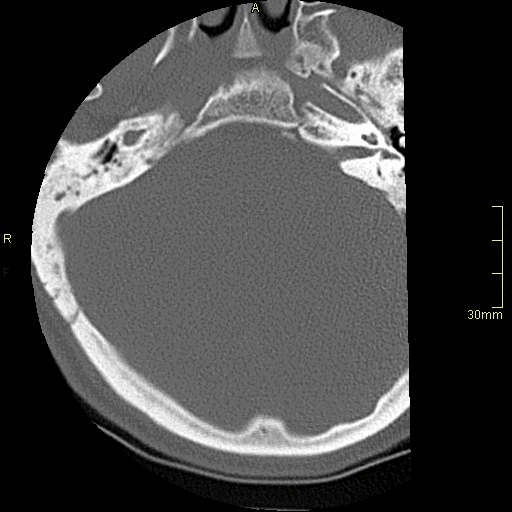

CT Cervical Spine Non Contrast- Bone window (axial)

CT Cervical Spine Non Contrast- Soft Tissue window (axial)